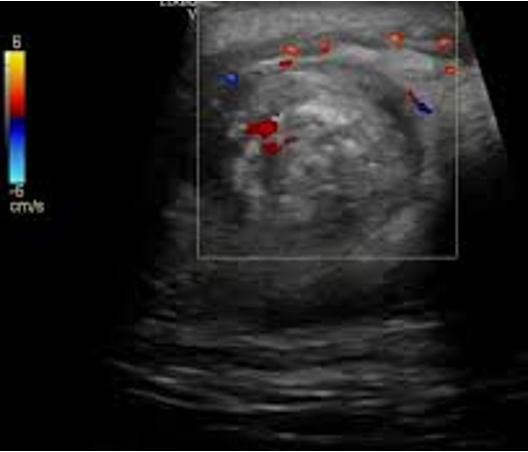

whirlpool sign

spiral-like pattern when the spermatic cord is assessed during ultrasonography